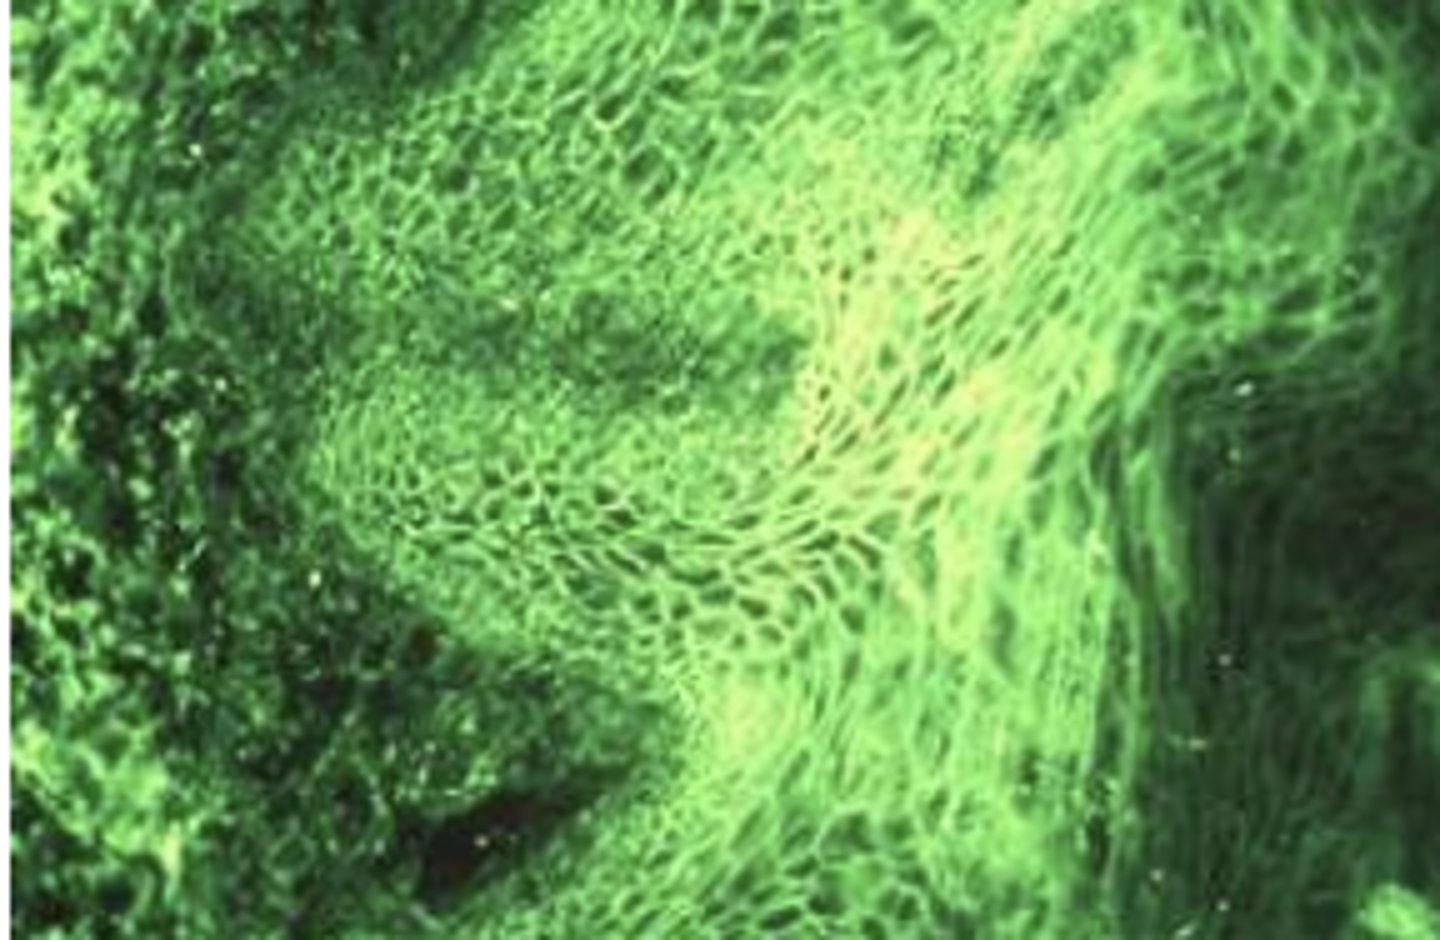

f. all of the above

Picture of inflammatory papillary hyperplasia. What are possible causes?

a. bad OH

b. negative pressure by form fitting denture

c. candida

d. A and B only

e. B and C only

i. Discontinue using denture for a period of time

ii. Improved oral hygiene

iii. Topical antifungal therapy (may be helpful)

iv. Tissue conditioner may reduce problem (mild cases)

v. Surgical removal of hyperplastic tissue (severe cases)

1. Scalpel/Cautery/Laser

vi. May need new denture fabricated

Inflammatory papillary hyperplasia was asymptomatic, scenario: pt is using half a thing of denture glue to hold it in place. What is tx?